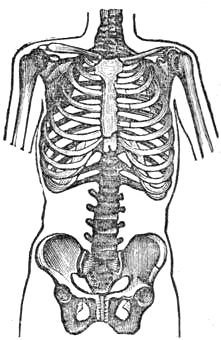

| 250. | HOW WASP WAISTS ARE MADE, | 799 |

| 251. | A CONSUMPTIVE WAIST, | 800 |

| 252. | NON-CONSUMPTIVE WAIST, | 800 |